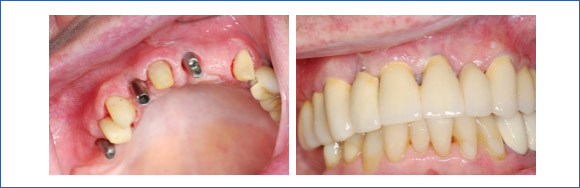

Bei der Versorgung von großen Schaltlücken dient die Pfeilervermehrung zur Stabilisierung des Restgebisses.

Freiendversorgung mit einer Brücke:

Einzelzahnersatz:

Eine Brückenversorgung kann oftmals vermieden werden. Der Vorteil ist, dass gesunde Nachbarzähne nicht beschliffen werden müssen.